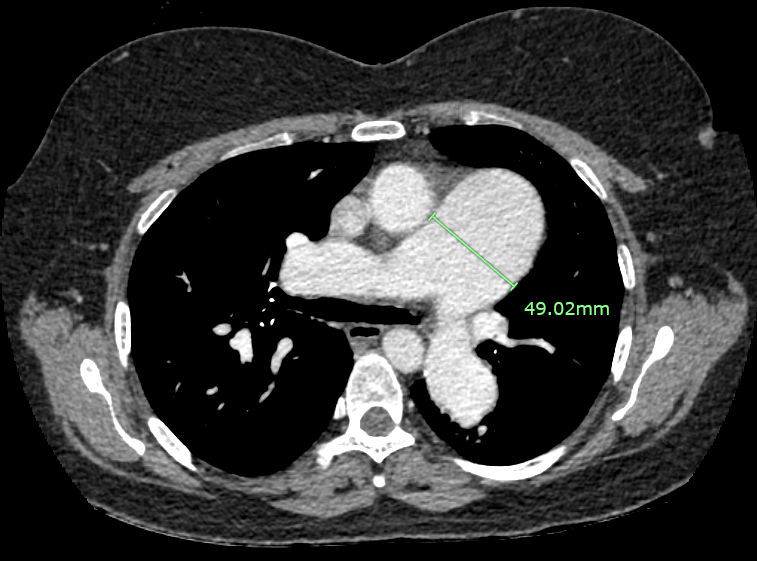

CT scan (CTPA and CT coronary) : Resolved pulmonary artery thrombosis, Normal epicardial coronary arteries. ASD measures 3.2 x 2.9 cm

CT scan (CTPA and CT coronary) : Resolved pulmonary artery thrombosis, Normal epicardial coronary arteries.

This case highlights our patient with longstanding secundum ASD and pulmonary arterial hypertension who developed dynamic left main coronary compression by a dilated pulmonary artery, confirmed on IVUS (MLA 12.8¡æ6.7 mm©÷, minimal plaque). Cardiac MRI showed Qp:Qs 1.86 and right-sided dilatation; right-heart catheterization revealed elevated but partially reversible PVR (4.9¡æ3.8 WU with iNO). A multidisciplinary, safety-first ¡°treat-and-reassess¡± strategy (targeted PAH therapy with planned fenestrated ASD closure if PVR improves) avoided premature high-risk interventions and provides a practical framework for similar complex ACHD patients.